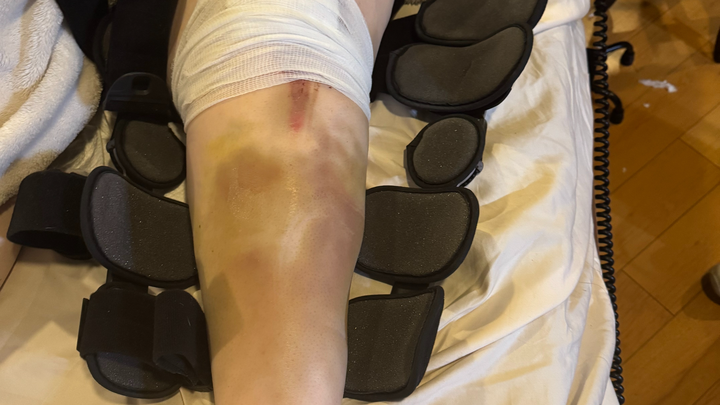

Many of you know that I was in a pretty serious motorcycle accident in February this year, which required emergency surgery on my arm, and I'm still waiting to get approval for a knee replacement. UCI Hospital just wrapped up their billing, and I am left with a crushing copay of $24,363.98!!! I am reaching out to my friends and family for help. This is completely devastating. People with insurance should not be left with this kind of life-crushing debt if they are in an accident. I was initially taken to UCI Trauma Center because it was the closest, and my situation was critical. I had Kaiser insurance, but because Kaiser was too overcrowded, they had me remain at UCI for the surgery and recovery, but they processed the claim as out of network. I didn't have a choice!! I was broken and helpless!!